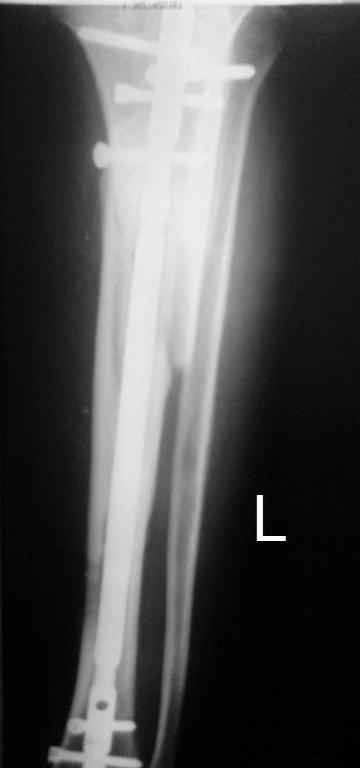

Тогда можно рассмотреть вопрос одновременного удаления штифта, мышечной (в данной области применим проксимально отсеченный лоскут камбаловидной мышцы) или микрохирургической (что более надежно) пластики дефекта мягких тканей, остеотомии проксимального фрагмента большеберцовой кости, остеосинтеза блокируемым штифтом с а/б покрытием, наложения простого аппарата Илизарова (можно из полуколец) для дистракции на штифте. При данном варианте пациент сохраняет возможность полной опоры на ногу, что очень важно для заживления у пожилого пациента) и отпадает необходимость в проведении дополнительный операций (при благоприятном развитии событий).

Выкладываю картинки похожей пациентки. Извините, что без окончательных снимков (сейчас их нет под рукой). Правда мы имели проблемы у данной больной после снятия аппарата, когда промежуточный фрагмент большеберцовой кости сместился на 1,5 см дистально и отошел от проксимальной части кости. До сих пор у пациентки на снимках определяется лишь тонкая полоска кости по задней поверхности за штифтом (образовалось что-то вроде маленького регенерата)в области стыковки промежуточного и проксимального фрагментов. Больная пока решила подождать. Не хочет оперироваться, так как ходит не хромая, работает.